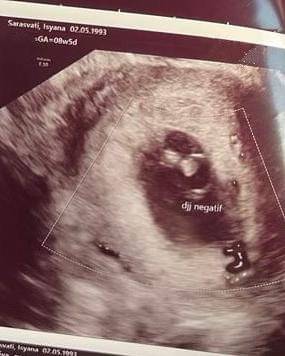

11. Baru saja keguguran anak pertama di usia kandungan delapan minggu

Telah mengarungi bahtera rumah tangga selama tiga tahun lamanya, tak heran jika kehadiran momongan menjadi salah satu hal yang dinantikan oleh Isyana dan Rayhan. Terbaru, Isyana dikabarkan mengalami keguguran di usia kehamilan delapan minggu.

Berita duka tersebut dibagikannya langsung melalu unggahan di Instagram pada Selasa (10/10/2023). Dalam unggahan tersebut, Isyana memperlihatkan foto hasil USG yang menunjukkan tanda janinnya sudah tidak ada.

Penyanyi kelahiran 1993 ini menuliskan salam perpisahan kepada janin yang pernah ada di kandungannya. Ia mengucapkan rasa terima kasih kepada si Kecil yang sudah berjuang bersama sebelum dinyatakan telah tiada.